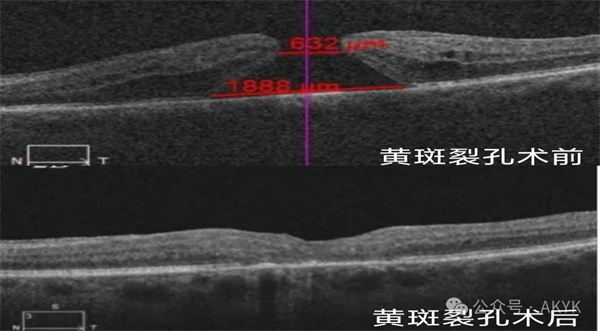

新業(yè)務二

復雜黃斑裂孔修復術:修補裂孔提升視力,降低致盲率。